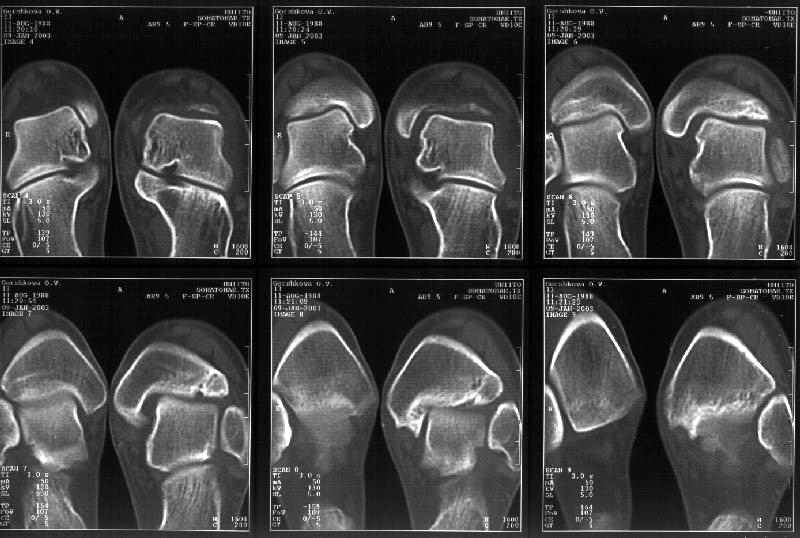

Сегодня пациентке сделали сравнительную КТ. А ксиальные и Фронтальные срезы приложены. Ваше мнение?

Фронтальные